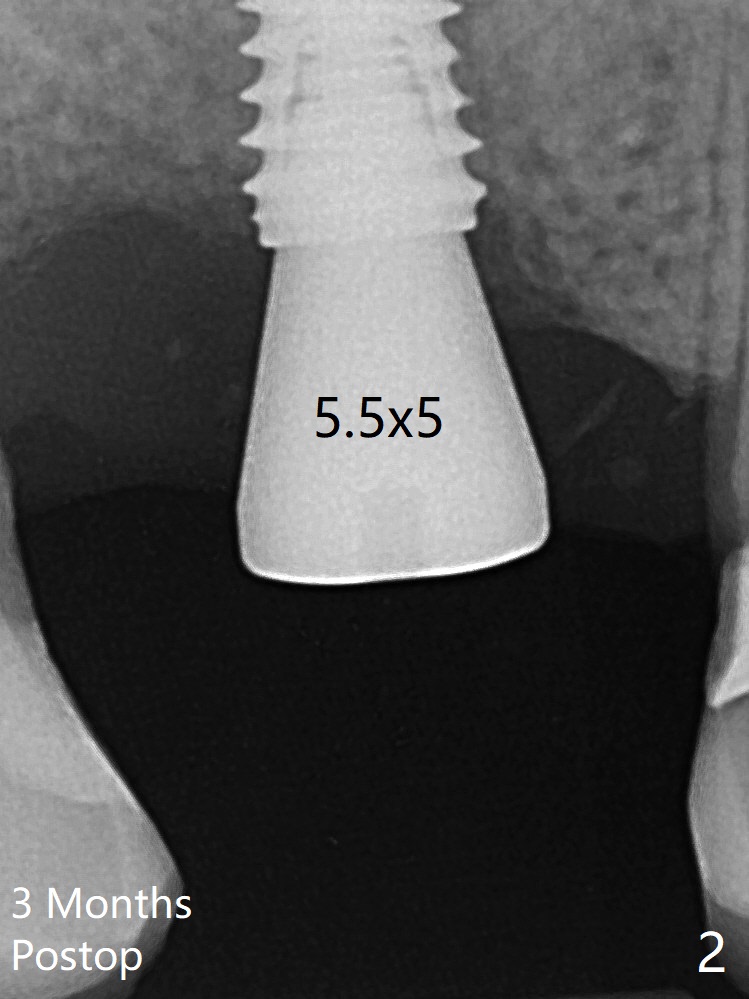

愈合基台术后三个月脱落,他再次要求修复,甚至提出退款,不愿意回诊所,因为他有糖尿病,新冠病毒高危人群。 放置小号愈合基台(图二)。他原来托牙是Valplast,没有occlusal rests,不能经过修改临时使用,可能将直接放置修复基台做临时牙冠。放置修复基台后(图三(术后三个月)),制作临时牙冠时,发现前者有些松动,后者就没有粘固。当基台完全就位,它最冠方与植体没有间隙(箭头),根方有间隙(空心箭头)。其实愈合基台也是一样(图一,二)。